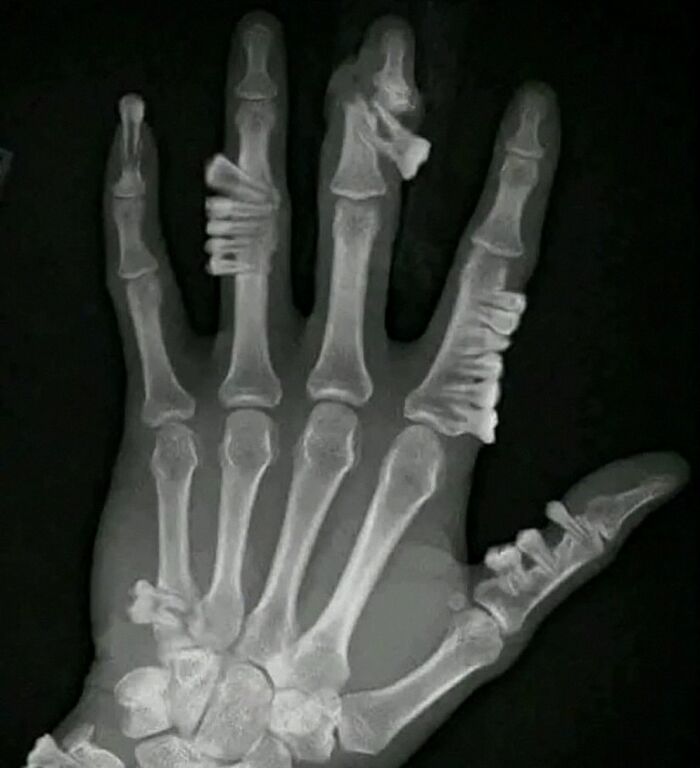

Don't bite the hand that feeds you. Also, don't grow teethy palms. Or v****a dentata